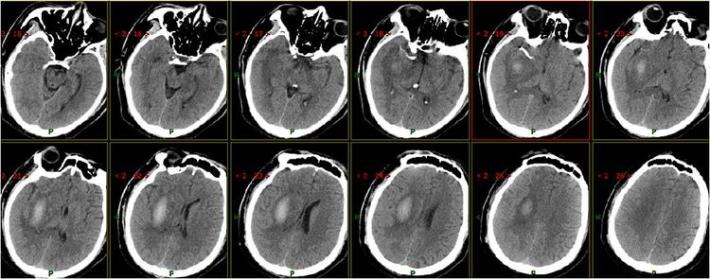

术后即刻复查头部CT

患者术后1天,左侧肢体肌力0级,NIHSS评分:12分,复查头部CT:右侧基底节区出血,范围约22mmX49mm,请脑外科会诊:做好立体定向穿刺准备,注意观察患者病情变化,密集复查头部CT。

术后3天复查头部CT

术后7天复查头部CT

术后15天复查头部CT

术后21天复查头部CT